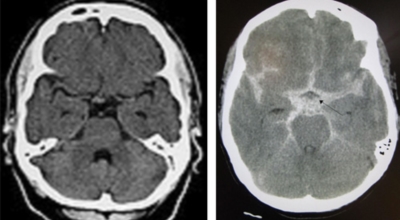

뇌졸중 종류

뇌졸중은 뇌경색과 뇌출혈 두가지로 나뉘게 돼요. 먼저 뇌경색은 뇌혈관이 막혀 영양분과 산소를 주는 피가 통하지 않는 상태로 원은은 크게 세 가지로 나눌 수 있는데요 동맥경화증이 생겨 좁아진 부위로 인하여 혈액공급이 부족해지거나 좁아지다가 결국 막혀버리는 경우, 큰 혈관에서 분지한 작은 혈관들이 고혈압 등으로 압박을 받으면 혈관이 막히는 경우가 있습니다.

또한 심장 판막질환이나 심방세동 또는 심근병 등등의 심장 질환이 있는 경우 심장에서 혈전이 만들어지고 그게 뇌로 흘러가게 되면 뇌혈관을 막게 되는 경우가 있답니다. 뇌출혈은 뇌경색과 반대로 뇌혈관이 터져서 생기는 뇌내 출혈과 거미막하 출혈로 나누게 돼요. 거미막하출혈은 혈관벽의 약한 부분이 부풀어 오르는 뇌동맥류가 터지는 경우와 관련성이 크다고 해요.